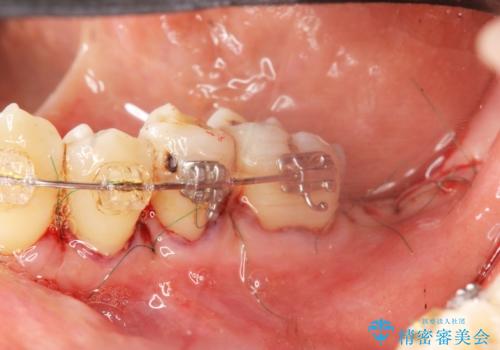

歯周病再生治療と歯周ポケット除去 歯周外科手術

- 他院で歯周病を指摘され、様子見ではなく根本的な治療はないか?とご相談に来院されました。

重度の歯周病で再生療法の適応ではない最後方臼歯は抜去行い、インプラント治療、

がたつきの強い天然歯を矯正治療で整えたのち、再生治療、歯周ポケットを除去する歯周外科手術を行いました。

歯周病の問題が解決したのち、歯の揺れを抑えるべくセラミッククラウンで連結補綴をおこなっています。

再生療法を行ったことで、抜歯をされてもおかしくなかった歯を、残すことができました。